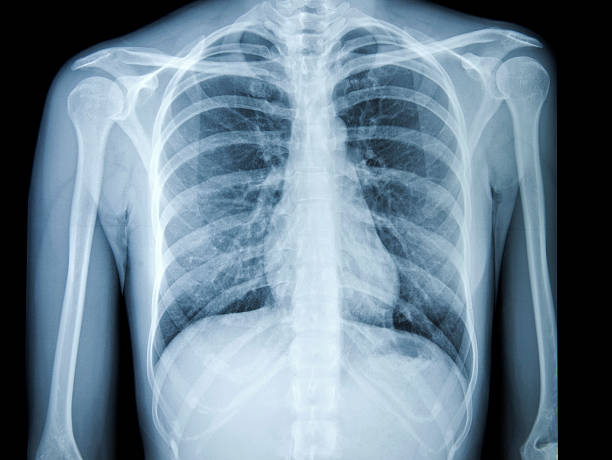

부러진 갈비뼈에 대해 자세히 알아보기

갈비뼈가 부러지면 갈비뼈 주변 조직에 염증이 생깁니다., 근육 및 인대 자극은 다양한 증상을 유발할 수 있습니다.. 갈비뼈가 부러졌을 때 나타날 수 있는 증상은 다음과 같습니다..

부러진 갈비뼈가 아프다, 그것은 또한 당신이 무감각하게 만들 수 있습니다. 특히, 통증은 호흡이나 움직임에 따라 증가할 수 있으며 주변 조직을 자극하여 열감을 유발할 수도 있습니다..

갈비뼈 주변 조직의 염증은 부종을 유발할 수 있습니다.. 부러진 갈비뼈로 인한 붓기, 갈비뼈 주변의 근육이 아플 수 있습니다..

갈비뼈가 부러진 경우, 숨을 쉴 때 갈비뼈가 움직일 때 통증이 발생할 수 있습니다.. 이것은 때때로 호흡을 어렵게 만들 수 있습니다..

갈비뼈가 부러진 경우, 감염이 발생할 수 있습니다. 이 경우, 증상으로는 갈비뼈 주변의 붓기와 분비물이 포함될 수 있습니다.. 또한, 감염은 또한 발열 및 오한과 같은 증상을 유발할 수 있습니다..

갈비뼈가 부러진 경우, 폐로 들어가 폐쇄성 폐질환을 일으킬 수 있습니다.. 이 경우, 호흡 곤란, 기침, 천식과 같은 호흡 문제가 발생할 수 있습니다..

갈비뼈가 부러진 경우, 갈비뼈 주위의 혈관을 손상시켜 출혈을 일으킬 수 있습니다.. 이 경우, 가슴 통증, 호흡 곤란, 헤모글로빈 감소와 같은 증상이 나타날 수 있습니다..

갈비뼈가 부러진 경우, 심장 근육을 자극하여 심장마비를 일으킬 수 있음. 이 경우, 협심증의 증상이 나타납니다., 가슴 통증, 호흡 곤란, 심장 부정맥이 발생할 수 있습니다..

금속이 갈비뼈로 갈 때, 갈비뼈 구조를 파괴하고 갈비뼈 골절을 유발할 수 있습니다.. 이 경우, 갈비뼈 부위의 통증, 부종, 창백한 피부색 등이 나타날 수 있습니다..

갈비뼈가 부러졌을 때, 증상은 환자의 상태와 눈물의 정도에 따라 다를 수 있습니다.. 그러므로, 균열이 있으면 즉시 의사와 상담해야 합니다.. 금속이 갈비뼈 주변 조직 깊숙이 침투하거나, 감염 등의 합병증이 발생할 수 있기 때문입니다..